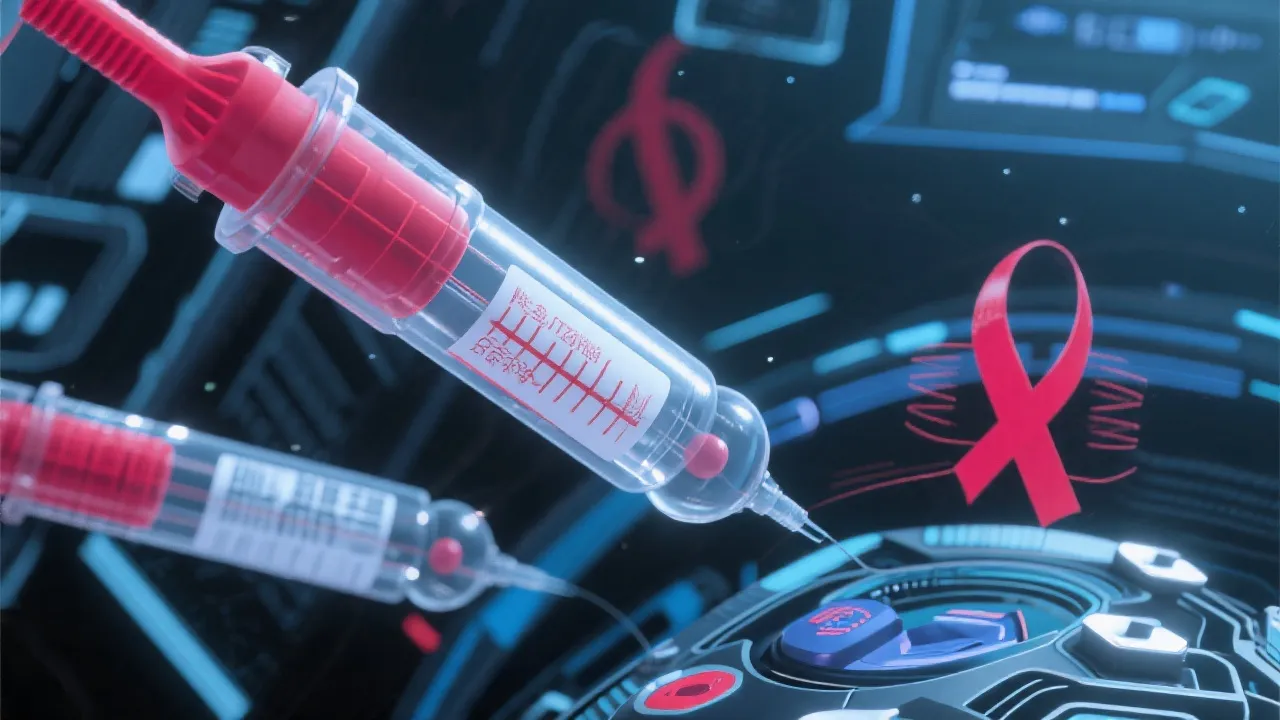

Advances in HIV Therapeutic Strategies

Therapeutic Strategies Against HIV

Innovative Therapeutic Strategies Against HIV

Innovative Therapeutic Strategies Against HIV

Innovative Therapeutic Strategies Against HIV

Innovative Therapeutic Strategies in HIV Treatment

Advanced Therapeutic Strategies Against HIV

Innovative Strategies Against HIV

Innovative Therapeutic Strategies Against HIV

Innovative Therapeutic Strategies Against HIV

Innovative Therapeutic Strategies Against HIV

Comprehensive HIV Therapeutic Strategies